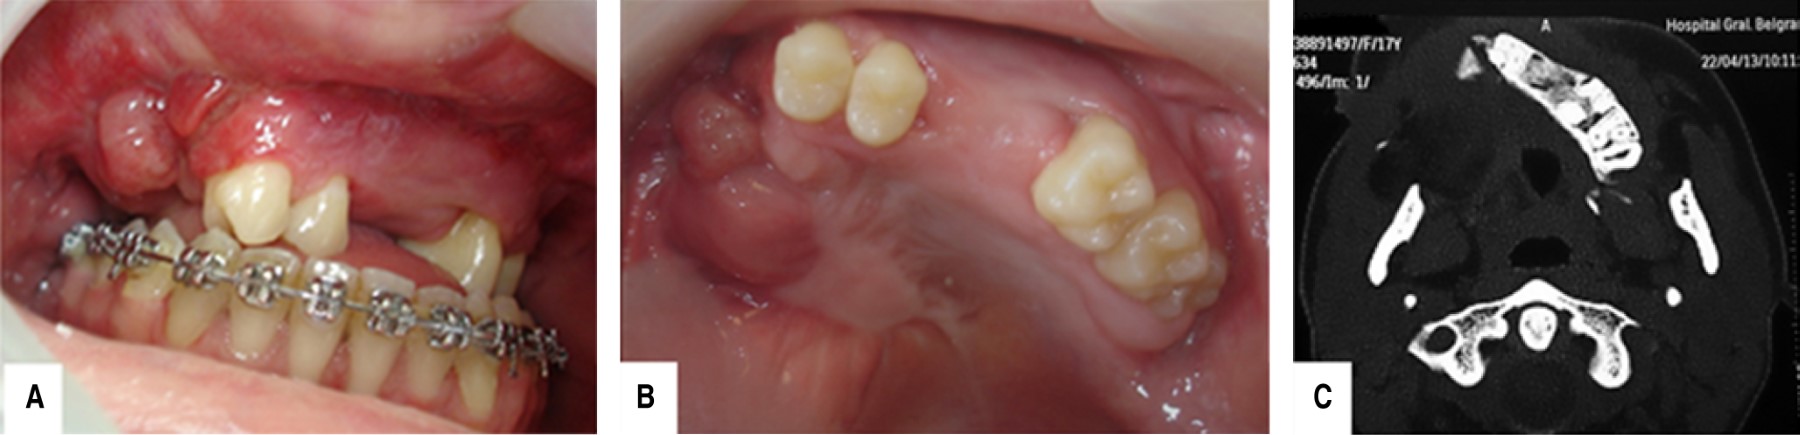

Juvenile trabecular ossifying fibroma maxillary with sarcomatization: 18-years follow-up

Ossifying fibroma a benign neoplasm of fibro-osseous tissue, with well-defined limits histologically characterized a large amount of fibrocellular and mineralized tissue. This pathology is classified two categories, including juvenile trabecular ossifying fibroma (TrOF) and psammomatoid (PsOF). Although the characteristics of these lesions are presented in a similar way, the great difference between them is the average age of presentation: 6-11.5 years the trabecular and from 12-18.9 years older the psammomatoid. Between these two groups there are histological variants and among them is the possible and unusual presentation of malignancy within the histology. The aim of this report is to describe the treatment of an eight-year-old female patient with a diagnosis of highly aggressive juvenile ossifying fibroma with points of possible sarcomatous transformation in maxillary without recurrences clinical, radiographic and tomographic follow-up for 18 years.